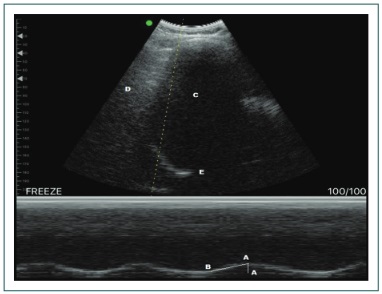

El ultrasonido diafragmático ha ganado un lugar junto con los predictores ya existentes para la valoración del retiro de la ventilación mecánica, hasta el momento con pruebas como la detección de edema pulmonar, el movimiento diafragmática, la distancia que el diafragma es capaz de moverse durante el ciclo respiratorio y la fracción de espesor diafragmática (FED), que es la relación entre la diferencia en el espesor en inspiración y la espiración dividida entre el grosor en espiración (FED = FEI − FEE)/FEE), y por último, el tiempo inspiratorio máximo diafragmático de cada hemidiafragma (Fig. 4).51,52,53,54

Valoración diafragmática. A-A: movimiento diafragmático; A-B: tiempo inspiratorio máximo diafragmático; C: parénquima hepático; D: parénquima pulmonar; E: diafragma.